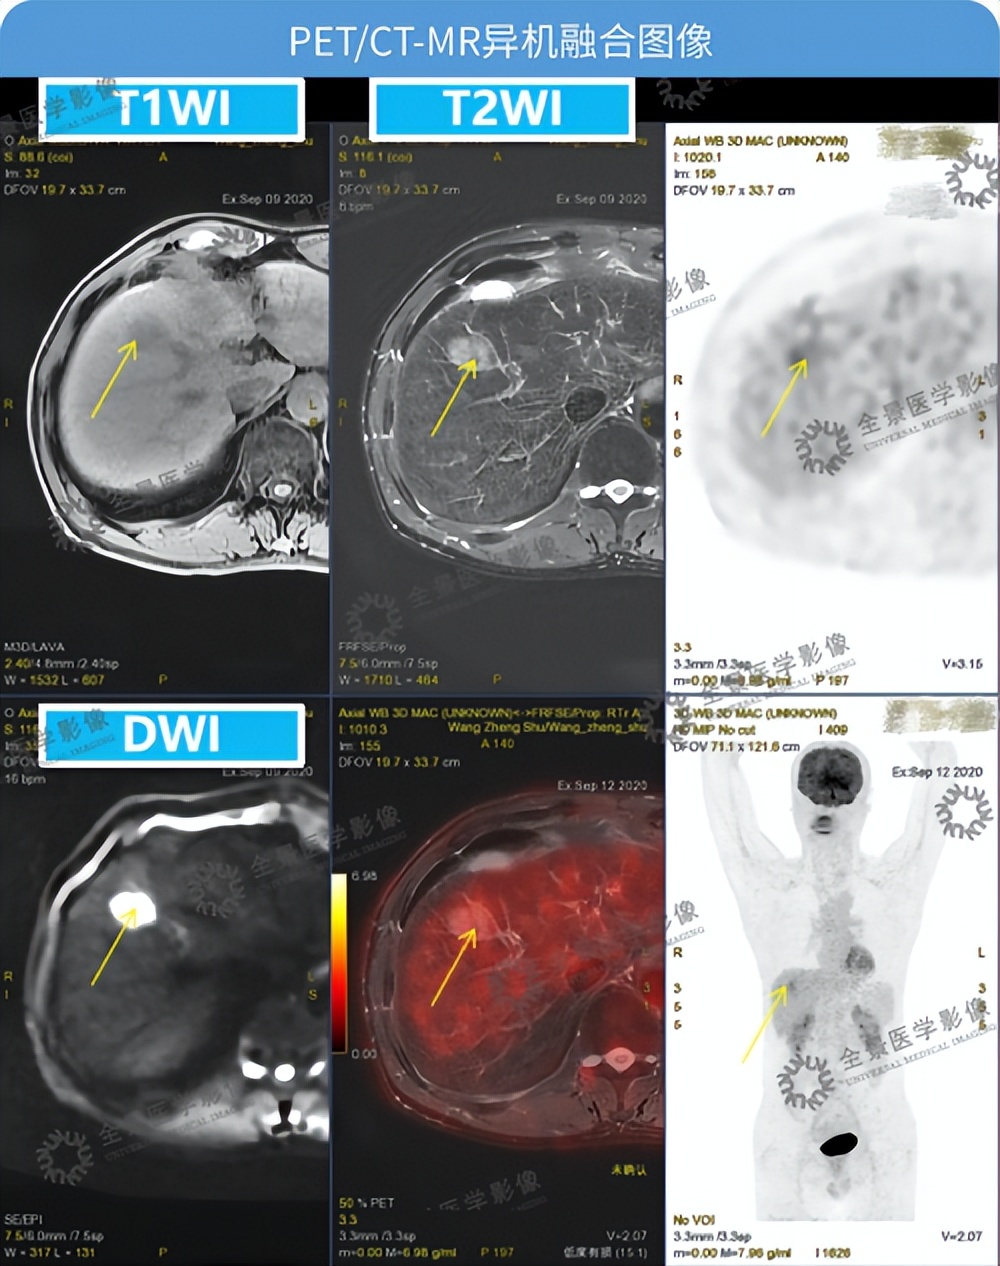

不出意外的,磁共振再次确认了我的肝部有团块状的阴影,增强扫描持续强化。

肿瘤标志物AFP的检测结果也出来了,左边是0-25ng/mL的正常参考值,右边我高达800+指标异常醒目,心里那一丝的侥幸顿时荡然无存。

PET/CT结果出来后,全景又与我的磁共振检查图像进行融合,最后诊断为肝癌。